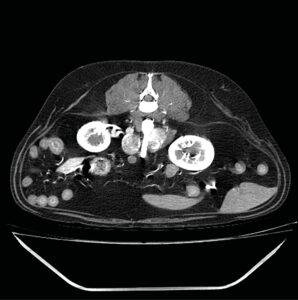

En estudios de TC sin contraste los feocromocitomas se observaron con valores más altos de Unidades Hounsfied (UH) con una atenuación media de 44,5 UH mientras que, en los adenocarcinomas, se observaron valores precontraste más bajos28,29. Esto puede deberse a que estos últimos se asocian con una mayor necrosis del parénquima o a que los feocromocitomas presentan con más frecuencia hemorragia intraparenquimatosa29. La angio-TC trifásica puede ayudar también a la diferenciación de las masas adrenales: se ha descrito que los feocromocitomas presentan una rápida captación de contraste en la fase arterial (imagen 6), mientras que los adenocarcinomas presentan un mayor realce en la fase venosa (imagen 7) y los adenomas un realce homogéneo en la misma fase32.

Imagen 6. Imágenes de TC plano transversal en ventana de tejidos blandos tras la administración de contraste en fases arterial (A) y venosa (B) de un feocromocitoma donde se observa un marcado realce en la fase arterial que disminuye y se vuelve más homogéneo en la fase venosa.